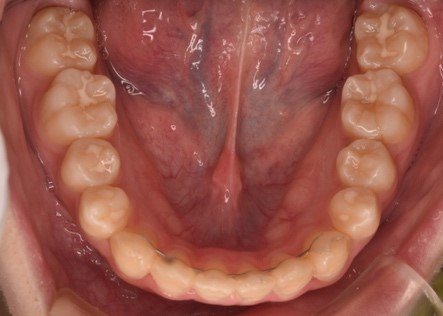

症例2 40代女性

「着色と歯並びが気になる」表面に付着した汚れを「クリーニング」で取り除き、マウスピース型矯正装置「インビザラインGO」で不揃いな並びの歯をきれいに改善した症例

| 診断結果 | 拝見したところ、下の前歯(左右中切歯/1番、側切歯/2番、犬歯/3番)は、デコボコに並ぶ「叢生(そうせい)」が見られました。 左上の前歯(側切歯)は、少し捻れて生える「捻転(ねんてん)」が見られました。また噛み合わせた時に、左下の前歯(犬歯)が左上の側切歯の前に出て逆に噛み合っている「交叉咬合」も認められました。歯の表面は着色の他に、白くねばついた汚れ「歯垢」や、それが固くなった「歯石」も付着していました。 レントゲン撮影で確認したところ、汚れはあるものの、虫歯はなく状態は良好でした。 |

| 治療内容 | まず歯のクリーニングを行い、汚れや着色を落としました。

歯並びに関しては、比較的短期間で改善ができるマウスピース型矯正装置「インビザラインGO」での矯正治療をご提案しました。奥歯の噛み合わせに問題がなく、前歯を動かすのに適していることをご説明し、同意いただきました。 治療前に、歯並びの変化をコンピューター上でシミュレーションした「クリンチェック」で、治療のイメージを確認しました。治療の際は、抜歯をせずに奥歯以外の20本の歯を動かし、歯並びを整えました。経過確認のため、お口の中の写真撮影や歯並びの状態を立体的な画像として見られる「口腔内スキャン」で矯正治療による歯並びの変化を見ていただき、毎回治療へのモチベーションが維持できるようにしました。 矯正終了後に、横に倒れて埋まっていた下左右の親知らず(第3大臼歯/8番)の抜歯も行いました。 |

| 術後の経過 | 歯の表面は、つやが出てとてもきれいになりました。歯並びも改善し、噛み合わせも問題なく、経過は順調です。

患者様は「歯並びがきれいになって良かった。いつまでも自分の歯で噛めるように、検診にもきちんと通いたい」と大変喜んでいただけました。 現在は、歯並びの後戻りを防止する「保定装置」を夜間のみ使用していただき、3ヶ月ごとにお子様と一緒に定期検診にご来院されています。 |